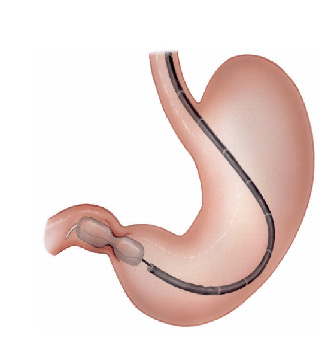

Gastrostomia endoscópica é a colocação de um tubo de alimentação diretamente para o estômago, através da parede abdominal.

Quando ela é usada?

Este procedimento pode ser feito para alimentar você, se você não consegue comer normalmente. Por exemplo, você pode precisar de uma gastrostomia se:

- Não puder engolir por algum problema como câncer de boca ou garganta, ou acidente vascular cerebral (AVC).

- Outros problemas para engolir (problemas de deglutição)

- Em alguns tratamentos médicos, como quimioterapia ou radioterapia, que são temporários mas as vezes tornam difícil você comer o suficiente para obter uma boa nutrição.

- Casos de desnutrição severa.

Alguns tubos de alimentação temporários são passados através do nariz até o estômago, são as chamadas sondas nasoenterais. Um tubo de gastrotomia é normalmente colocado para permitir a remoção de uma sonda nasoenteral, de modo que a alimentação possa continuar com maior conforto e por tempo mais prolongado.

O que acontece durante o procedimento?

Para a gastrostomia endoscópica percutânea, você receberá um sedativo e um anestésico local para mantê-lo sem sentir dor. O médico irá introduzir um endoscópio através de sua boca até o seu estômago. Um endoscópio é um tubo fino e flexível com uma pequena câmera. Ele permite que o médico olhe para o interior de seu estômago durante o procedimento.

O seu médico irá encher o estômago com ar para torná-lo maior e empurrar a parede do estômago mais perto da parede abdominal. O médico irá guiar uma agulha e fio através de sua pele e parede abdominal até o seu estômago. O endoscópio permite ao médico ver e capturar o fio dentro do estômago.

O fio é então puxado de volta pela boca. Um tubo de plástico é ligada ao fio e puxado através da boca ao longo do percurso até o estômago.

O médico irá fixar o tubo de dentro do estômago e na sua pele. O pedaço curto do tubo de borracha visível através da parede abdominal é facilmente coberto com a roupa.